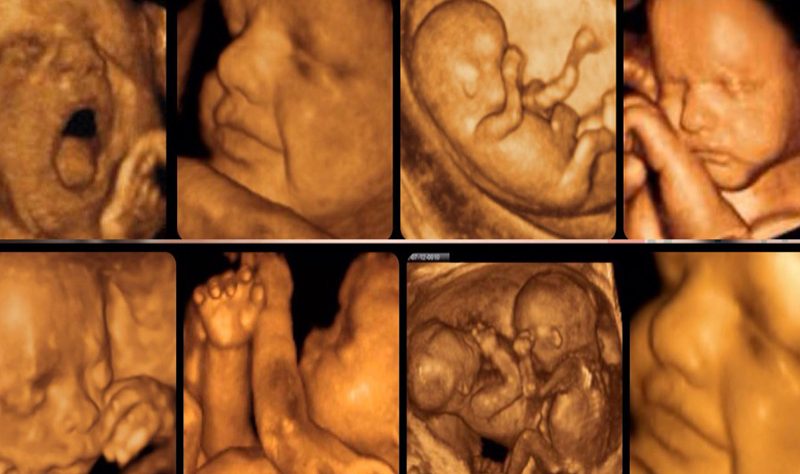

Dört Boyutlu Ultrason

Dört boyutlu (4D) ultrason, bebeğin üç boyutlu (3D) görüntülerinin zaman boyutu (hareket) eklenerek eş zamanlı olarak ekrana yansıtılmasıdır. Geleneksel siyah-beyaz (2D) ultrasondan farklı olarak, 4D ultrason teknolojisi sayesinde bebeğin esnemesi, parmağını emmesi veya gülümsemesi gibi hareketleri tıpkı bir video kaydı gibi canlı olarak izlenebilir.

- 4D Ultrason: 3D görüntülerin canlı bir film gibi hareketli halidir. Bebeğin o anki gerçek hareketlerini yansıtır.

4D ultrason gebeliğin her döneminde yapılabilir; ancak en net ve tatmin edici görüntülerin alınabilmesi için ideal zaman dilimi 22. ile 28. haftalar arasıdır. * Bu haftalarda bebeğin yüz hatları belirginleşmiş, cilt altı yağ dokusu artmış ve su miktarı görüntüleme için yeterli seviyededir.